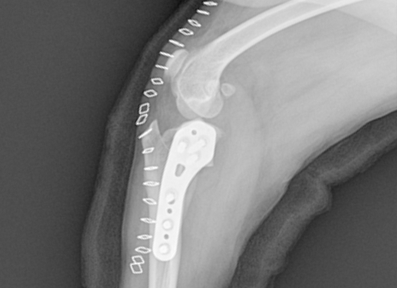

전십자인대 파열은 반려견에서 가장 흔한 무릎 관절 질환으로, 심할 경우 보행이 어렵고 심한 통증을 유발합니다. 본원은 뼈 구조, 체중, 활동 수준 등을 고려하여 TPLO, CTWO 등 다양한 수술 방법 중 가장 적합한 수술법을 선택해 맞춤 치료를 진행합니다. X-ray와 CT 영상을 통해 인대 손상 정도와 관절 상태를 정밀하게 진단하고, 수술 전 시뮬레이션을 통해 오차를 최소화합니다. 수술 후에는 통증 관리와 재활 운동, 근력 강화 프로그램을 통해 기능 회복을 돕고 재발을 예방합니다.